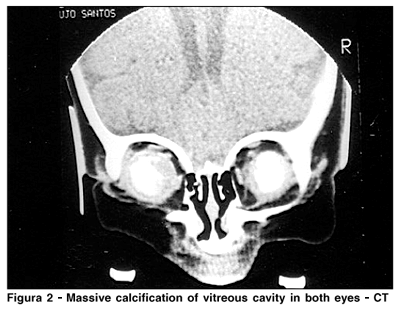

CT and ultrasonography showed similar features: plaques of calcification filling most of the vitreous chamber in both eyes ( Figure 2).

The amount of calcium in our case, plaques filling almost the whole vitreous cavity of both eyes (ultrasound and CT scan) is a very rare finding in retinoblastoma.